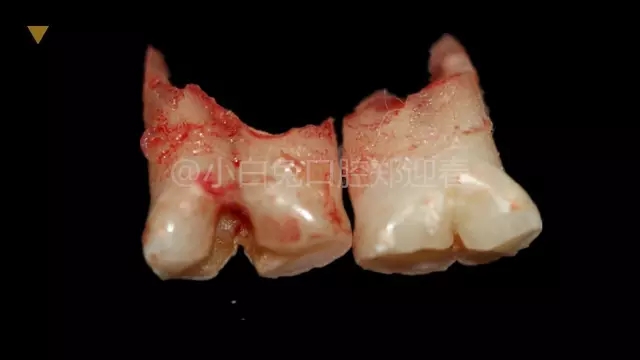

拔出后的離體牙

根據(jù)融合時(shí)間的早晚,可以形成冠根完全融合,也可以形成冠部融合而根部分離,或冠部分離而根部融合,臨床上所見到的多是牙冠部融合,這個(gè)時(shí)候的牙齒可以是一個(gè)根管,也可以是兩個(gè)根管。融合牙不但導(dǎo)致牙齒形態(tài)的異常,影響牙齒的形態(tài)美觀;還可以導(dǎo)致牙列的異常,導(dǎo)致牙體、牙髓、牙周疾??;還可能因?yàn)檠例X排列不整齊,導(dǎo)致咬合關(guān)系的不正常容易引起顳下頜關(guān)節(jié)疾病。